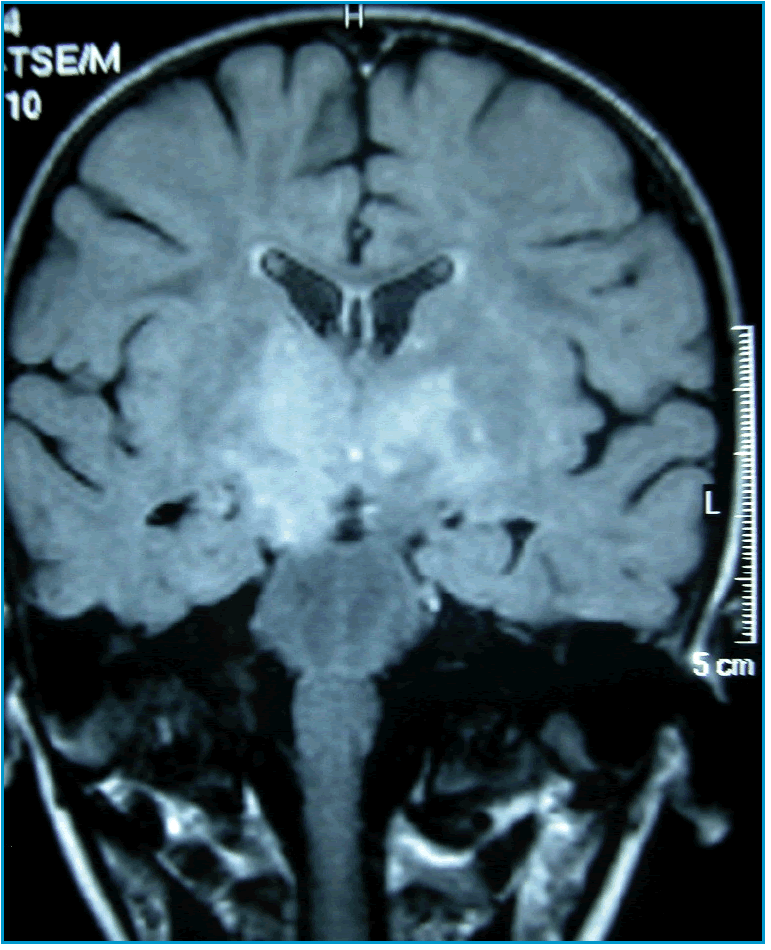

Fondamentale per la diagnosi è la RMN dell’encefalo e del midollo che mostra la presenza nelle sequenze T2-pesate di multiple aree iperintense che presentano caratteristicamente margini indistinti e assumono il mezzo di contrasto [4,5].

S., 2 anni, viene ricoverata per improvvisa comparsa di manifestazioni neurologiche (irritabilità, atassia, emiparesi, disestesia, strabismo) a breve distanza da un’infezione delle vie aeree superiori. Gli indici di flogosi sono negativi e l’esame del liquor evidenzia una modesta pleiocitosi linfocitaria con glicorrachia e proteinorrachia normali e assenza di bande oligoclonali. La RMN mostra multiple aree di iperintensità a livello dell’encefalo, in corrispondenza del talamo, del peduncolo cerebrale dx, dei gangli della base, del chiasma ottico e dei tratti ottici, e del midollo spinale, a livello di C3-C5, C7-D3, D7-D8 (Figure 1-3). Alcune delle aree captano in maniera disomogenea il gadolinio. Nel sospetto di ADEM la bambina viene trattata con boli di metilprednisolone e.v. (10 mg/Kg) per 5 giorni con rapido miglioramento dei segni neurologici. Il follow-up a 5 mesi documenta un’obiettività neurologica pressoché normale e una significativa riduzione delle aree iperintense, precedentemente rilevate, alla RMN.